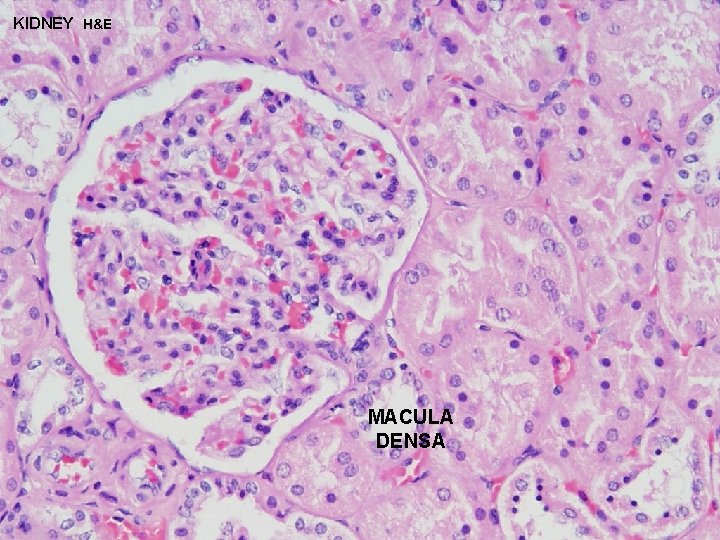

URINARY SYSTEM JUXTAGLOMERULAR MACULA DENSA + JUXTAGLOMERULAR (JG) APPARATUS CELLS REGULATE BLOOD FLOW THROUGH GLOMERULUS MACULA DENSA - cells located in the DCT in close contact with the glomerulus and the afferent and efferent arterioles JG CELLS - specialized smooth muscle cells in the wall of the afferent arteriole which contain and secrete RENIN to regulate blood flow through the glomerulus ANGIOTENSINGO GEN (PLASMA PROTEIN) RENIN ANGIOTENSIN II ALDOSTERONE SECRETION VASOCONSTR

KIDNEY H&E MACULA DENSA